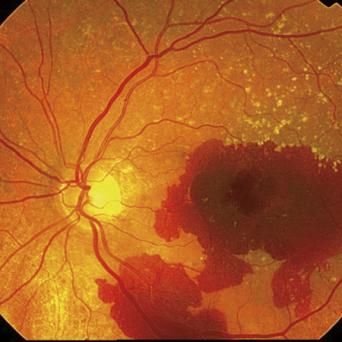

Œil rouge, blanc ou douloureux ?

En ville, le médecin généraliste est amené à voir 2 - 3 urgences ophtalmologiques par semaine. Sans matériel spécialisé, le diagnostic n’est pas toujours aisé. L'objectif de cet article est de fournir les clés pour évaluer la gravité des différents tableaux cliniques et proposer une prise en charge adaptée.